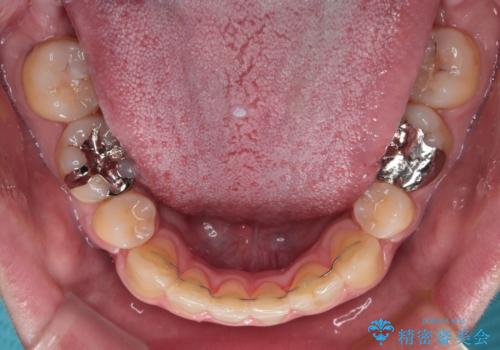

トレーニングをしっかりと行っていただいたため、スッキリとした口元に仕上がりました。